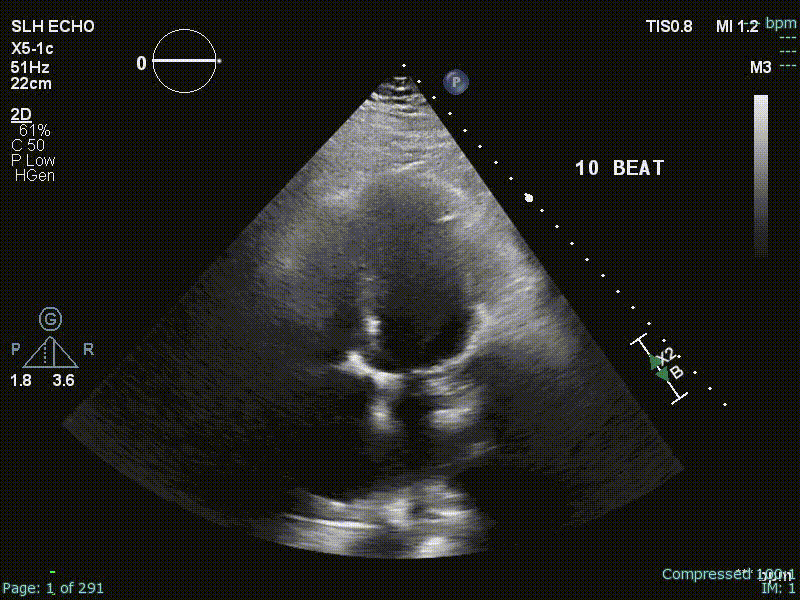

Echo

“Echo diagnosis of constriction is all about pattern recognition” - Sanjiv Shah

Ventricular Interdependence? Think constriction

Constrictive physiology should be considered when evidence of enhanced interdependence is observed by echocardiography.

- Diastolic septal bounce

- Ventricular interdepence and Respirophasic Variation

- Dilated IVC